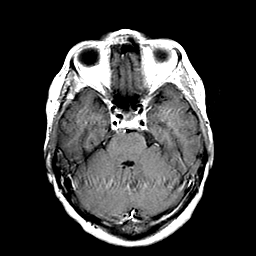

Metastatic Adenocarcinoma of the Colon: T1-weighted MR -- Slice #8

[Home][Help][Clinical] Slice 8